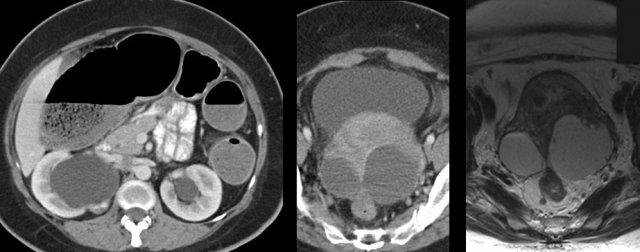

Ở bệnh nhân nữ trẻ này với các triệu chứng đau bụng mạn tính không rõ nguyên nhân kéo dài nhiều năm, CT và MRI tiếp theo đã phát hiện lạc nội mạc tử cung lan rộng.

Ngoài ra, còn ghi nhận các nang lạc nội mạc tử cung lớn có dính (“buồng trứng hôn nhau”), ứ nước thận hai bên và tắc nghẽn hoàn toàn đại tràng do lạc nội mạc tử cung xâm lấn vào niệu quản và trực tràng.